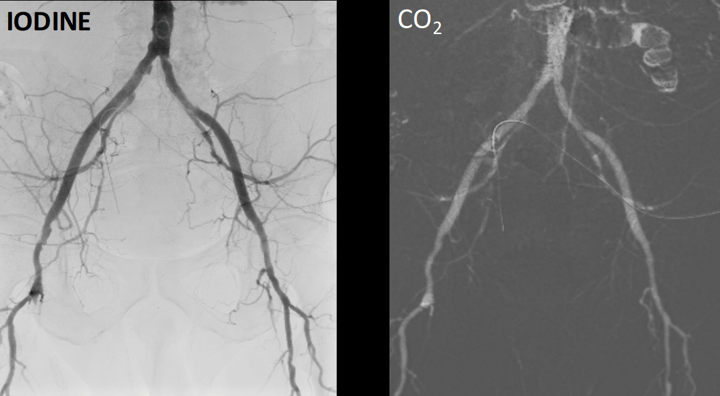

Throughout the years, the imaging technology has improved to a point that already impressive CO₂ images are virtually indistiguishable from ICM ones. This is a comparison between ICM and CO₂: